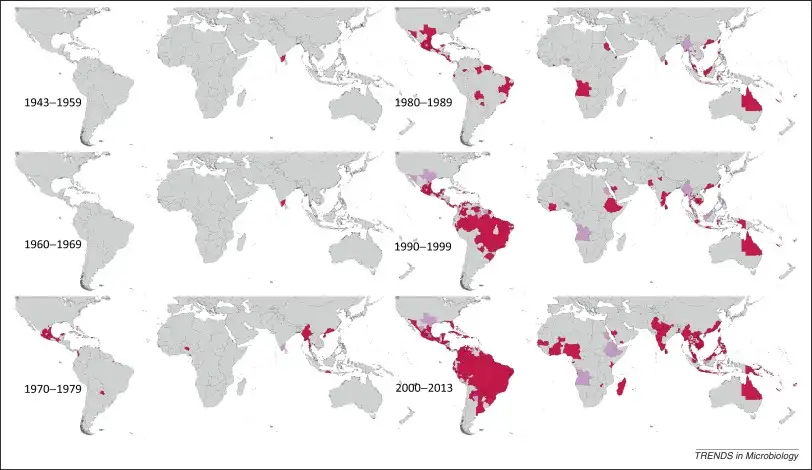

几乎在同一时间,遥远的雅加达和费城也报告了类似的疫情。这是人类历史上首次有明确记录的登革热大流行。然而,当时没有人知道,这种疾病将在接下来的两个半世纪里,成为人类与蚊子之间最漫长、最残酷的战争之一。今天,登革热已成为全球最常见的虫媒病毒疾病,每年感染约四亿人,导致约两万人死亡。它最令人胆寒的特征,不是它传播的广泛性,而是它独特的"背叛"机制——它能够利用人体免疫系统产生的抗体,作为入侵细胞的钥匙,让曾经保护你的盾牌变成刺向自己的利刃。

从非洲丛林到全球蔓延:伊蚊的殖民史诗

登革热病毒的传播媒介主要是埃及伊蚊(Aedes aegypti),这种小型蚊子有着独特的黑白条纹,胸部背面有一个类似七弦琴形状的白色图案。埃及伊蚊原本生活在非洲的丛林中,以吸食野生动物的血液为生。但随着大航海时代的到来,这种蚊子开始了它的全球殖民之旅。

15世纪至19世纪,跨大西洋奴隶贸易将数百万非洲人运送到美洲。与此同时,埃及伊蚊的卵也随着奴隶船上的水桶漂洋过海,在新大陆安家落户。到17世纪,埃及伊蚊已经遍布加勒比海、中美洲和南美洲的沿海城市。这种蚊子完美地适应了人类的生活环境:它喜欢在人工容器中繁殖——花盆、水桶、废弃轮胎、甚至一个小小的瓶盖中的积水都足以让它繁衍后代。

20世纪中期,人类曾有一次消灭埃及伊蚊的机会。1947年,泛美卫生组织启动了大陆性的埃及伊蚊根除计划,目标是消灭传播黄热病的蚊子。在DDT等杀虫剂的助力下,到1962年,18个大陆国家和多个加勒比岛屿成功消灭了埃及伊蚊。然而,随着黄热病威胁的降低和政治意愿的消退,这项计划逐渐瓦解。蚊子迅速卷土重来,而这一次,它带来了登革热。

1981年,古巴经历了美洲历史上首次严重的登革热出血热疫情。超过34万人感染,10312例出血热,158人死亡。这场疫情的罪魁祸首是来自东南亚的DENV-2毒株,它比美洲本土的DENV-2毒株具有更强的致病性。此后,登革热在美洲持续蔓延,病例数呈指数级增长。2024年,美洲地区报告了超过1400万例登革热病例,创历史新高。

亚洲一直是登革热最沉重的负担地区。1953年至1954年,马尼拉首次报告了登革热出血热的流行。在接下来的二十年里,这种疾病蔓延到整个东南亚。印度、印度尼西亚、缅甸、斯里兰卡和泰国位列全球登革热负担最重的30个国家之中。在东南亚的一些城市,儿童在成年前感染登革热几乎是必然的宿命。

气候变化的礼物:登革热的新版图

全球变暖正在为登革热开辟新的疆域。温度是影响登革热传播的关键因素:它决定了蚊子的生存范围、繁殖速度、叮咬频率,以及病毒在蚊子体内的复制速度。研究表明,当气温从28℃上升到32℃时,登革热病毒的传播潜力可以提高一倍以上。

2024年发表的一项研究估计,历史上的气候变化已经使登革热的发病率平均增加了18%。如果全球气温继续上升,到本世纪末,可能有额外10亿人暴露在登革热的威胁之下。登革热正在向温带地区推进:欧洲南部、美国南部、日本和韩国都出现了本地传播的病例。2023年,意大利、法国和西班牙都报告了登革热的本地传播,这在几十年前是不可想象的。

国际旅行和贸易是登革热全球化的催化剂。一个感染登革热的旅行者可以在24小时内飞越半个地球,将病毒带到新的地区。如果当地存在埃及伊蚊,就可能引发本地传播。2013年至2016年期间,一项研究发现,在登革热流行的国家之间旅行的乘客数量增加了约25%,这与全球登革热病例的增加密切相关。